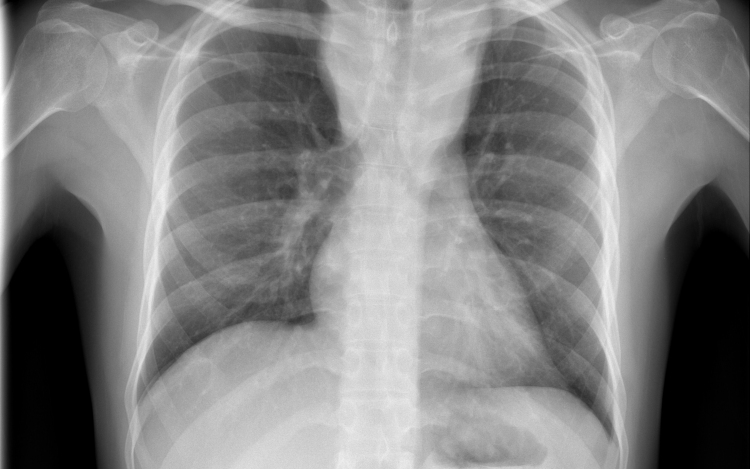

Átlagosan 4,3 százalékkal csökkent az új tuberkulózisos (tbc-s) esetek száma 2010 és 2014 között az Egészségügyi Világszervezet (WHO) 53 országot magába foglaló európai régiójában.

A becslések szerint 2014-ben 340 ezer európai betegedett meg tuberkulózisban, ami százezer emberre vetítve 37 esetnek felel meg. Azzal, hogy 2010 és 2014 között átlagosan 4,3 százalékkal csökkent az új esetek száma, az európai régió teljesítette azt a millenniumi fejlesztési célt, hogy 2015-re visszafordítja a tbc terjedésének tendenciáját.

Magyarországon biztonságos a tbc-re vonatkozó epidemiológiai helyzet: 2014-ben nyolc új eset jutott százezer lakosra, és az előzetes adatok szerint ugyanez igaz a 2015-ös évre is. Így a WHO Magyarországot az alacsonyan átfertőzött országok között tartja nyilván. Alacsony a multirezisztens esetek száma - 2014-ben hét új esetet észleltek -, valamint a gyermekkori megbetegedéseké is: 2014-ben hat 14 éven aluli gyermek betegedett meg.